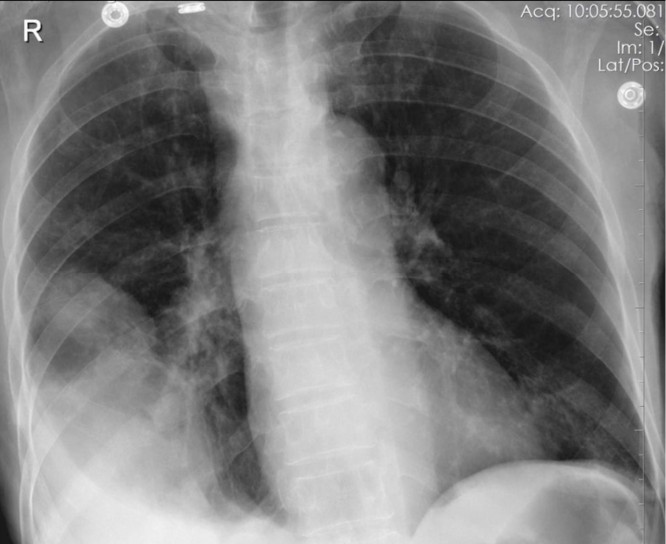

A 78-year-old woman presents with breathlessness. She completed a course of antibiotics for a mild pneumonia 1 week ago. Her history is significant only for hypertension and hypothyroidism. She stopped smoking 45 years ago.

1. What is the abnormality on this X-ray? 1 mark

You repeat a CXR.